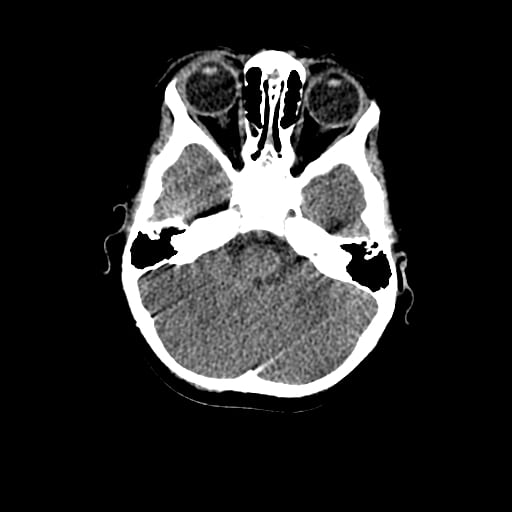

Age: 1

Sex: Male

Indication: Fall